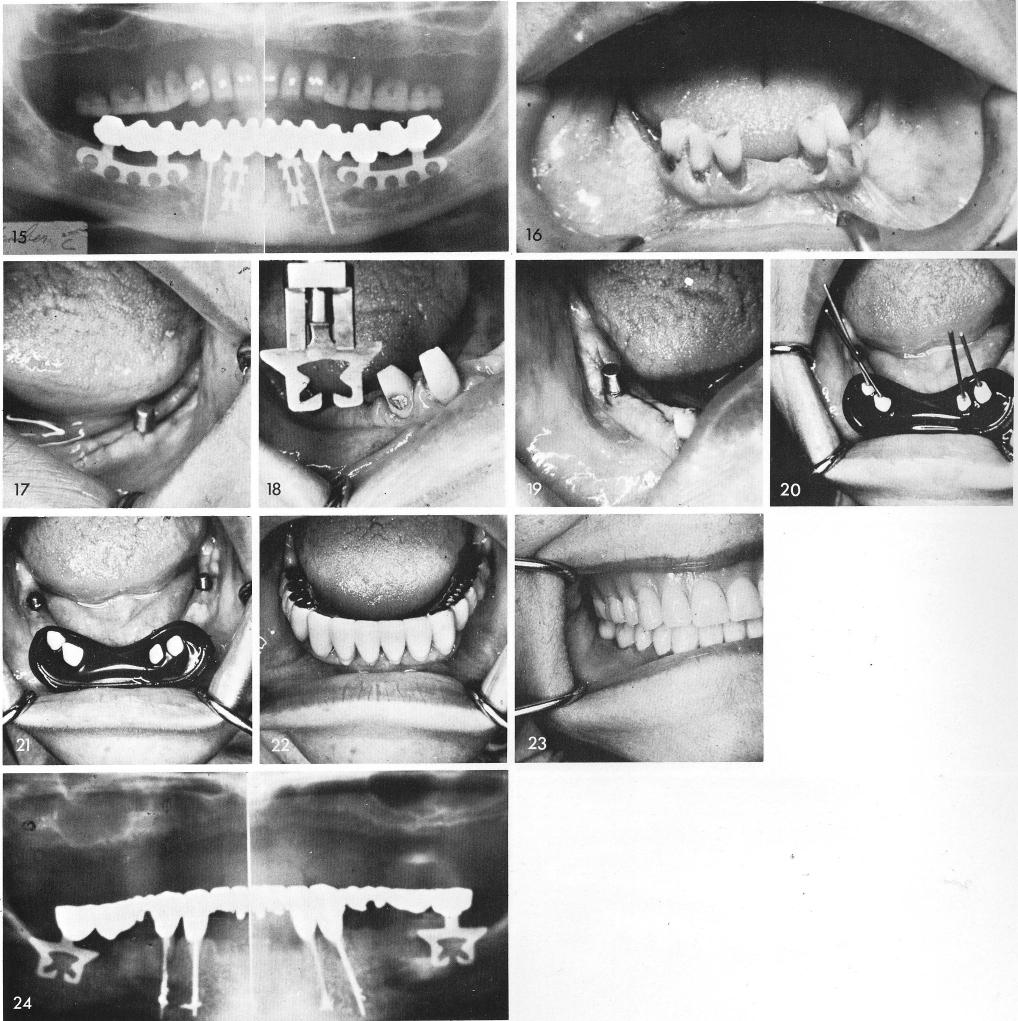

Similarly, other cases involving knife edge ridges posteriorly can still accept blades, figs. 16, 17, 18, 19. Anteriorly, without the use of midline blades, lengthening of the roots of the remaining teeth mechanically with the introduction of endodontic stabilizers helps to further the overall support of the entire prosthesis, figs. 20, 21. The completed prosthesis in place, figs. 22, 23, and the post-operative x-ray, fig. 24.